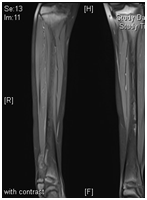

Figure 14 MRI of the lower limb showed aggressive bone lesion involving the distal diaphysis of the Right fibula associated with huge soft tissue tumor.

A Saudi girl, 10 years old presented to OPD with progressive swelling of the right ankle for 3 months, localized on the lateral aspect, and increasing with pain and swelling within last two months. During physical examination, proximal area of the skin over the swelling was dark black as what was noted. The patient was investigated primarily in a hospital outside of Riyadh according to a biopsy was taken with osteomyelitis of distal fibula and treatment was start taken but with no response. X-ray of the right leg (Figure 12) and CT of the lower limb (Figure 13). An expansile, lytic and destructive bone lesion is seen involving the distal third of the right fibula. (Figure 14) on MRI showed there is a large destructive bone lesion involving the distal third of the right fibula with sparing of the distal fibular epiphysis. No definite involvement of the right tibia and talus. Trace of fluid is seen in the right tibiotalar joint most likely reactive. The neurovascular structures appear intact. This was followed by technetium-99m MDP scintigraphy (Figure 15), what it showed a solitary focal lesion distal end of right fibula compatible with suspected Ewing's sarcoma. No additional lesions were noted to suggest skip lesions or metastasis. She treated as per Ewing sarcoma protocol in our hospital. Patient was put on neoadjuvant chemotherapy. Later, We did a wide surgical resection of the tumor was preformed upto12 cm from the distal fibula malleolus during which ,the superficial peroneal nerve and peroneus longus and brevis tendon were sacrificed the ruminant of the peroneus longus and calcaneo fibular ligament were sutured and using anchors were attached to the distal tibia in the right leg free pedicle latissmuss dorsi flap was anastomosed to the peroneal artery locally to cover the soft tissue defect by the plastic surgery team. The last MRI done for the patient (Figure 16) showed there is interval reduction in the size of the previously noted heterogeneous enhancing mass at the distal metaphysis of the right fibula. On the bone scan (Figure 17), there is interval reduction in the size of the previously noted heterogeneous enhancing mass at the distal metaphysis of the right fibula. There is no sign of skip metastases to other limb. Bilaterally bone marrow signal changes are most likely related to chemotherapy. The patient will follow up with us regularly.